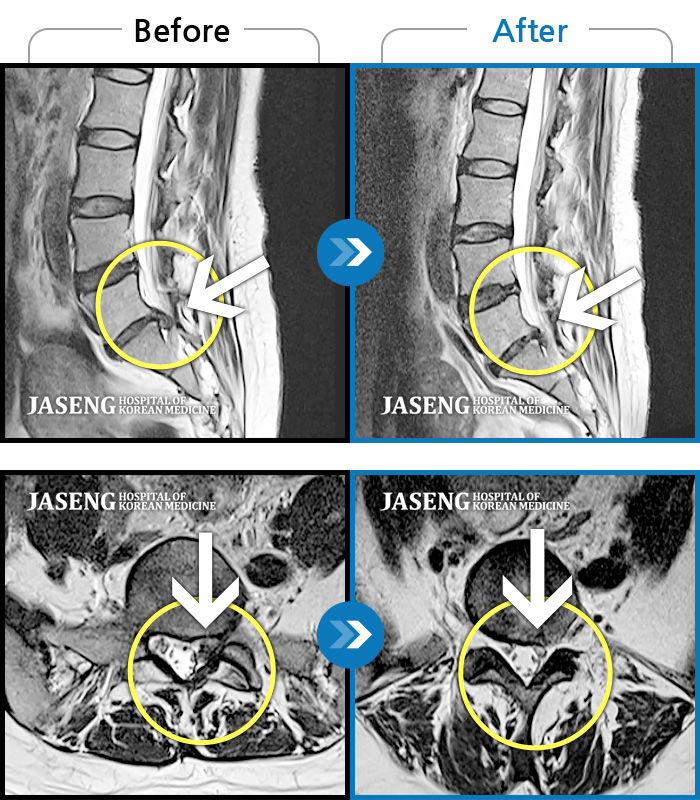

Before

After

환자에게 사전 동의를 받아 동일 조건에서 촬영되었습니다.

개인에 따라 치료 후 부작용이 발생할 수 있으니 의료진과 상담 후 치료를 진행하시기 바랍니다.

목을 들면 오른쪽 목 통증과 어깨 통증 발생, 오른쪽 어깨에서 팔꿈치까지 통증

기침하면 허리 통증 발생, 몸을 비틀면 우측 허벅지에서 종아리까지 통증